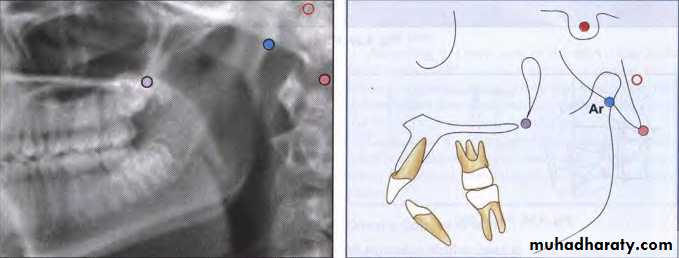

Articulare (Ar)

The intersection of the radiographic shadows:the inferior surface of the cranial base and the posterior

surfaces of the necks of the condyles of the mandible.

Articulare is systematically used for condylion when

the latter is not reliably discernible. Displacement of

the condyle moves the articulare.